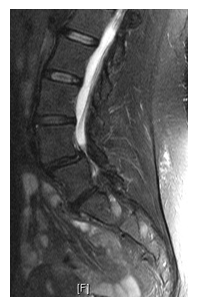

Minimal invasive spine surgery leads to fast recovery and makes patient walking after surgery within 24 hours. In fact in minimally invasive surgery and microendoscopic surgery and minimally invasive spinal fusion results in early return to work without any need of bed rest after surgery.

After surgery, the patient is mobilized out of bed within 24 hours, and pain medications are continued for 5 days. After the surgery, general do’s and don’ts instructions are given about. With Minimal, Invasive spine surgery patient can go home within 48 hrs and can resume job within 2 weeks however Contact sports is generally avoided for 6-10 weeks.